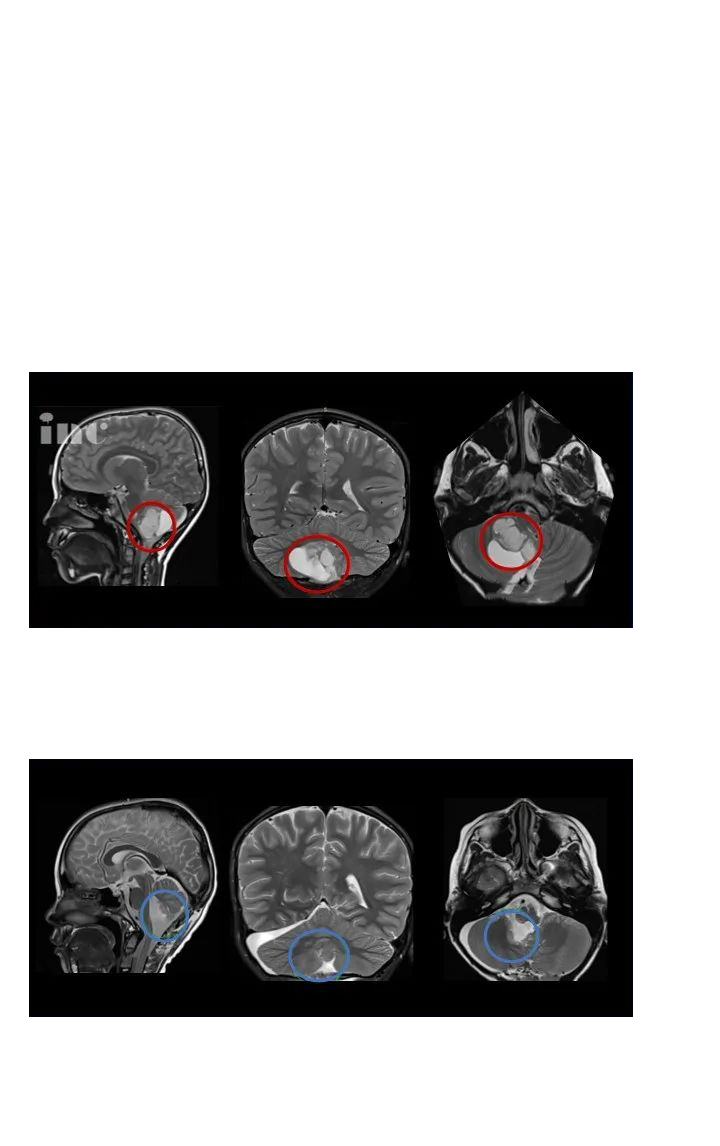

【圖.術(shù)前(a)和術(shù)后(b)顱腦磁共振MR,術(shù)前MR顯示右側(cè)丘腦較大囊實(shí)性占位,膠質(zhì)瘤可能,皮質(zhì)脊髓束(負(fù)責(zé)人體肢體運(yùn)動的神經(jīng)傳導(dǎo)束)受壓,腦室擴(kuò)大,術(shù)后MR顯示腫瘤全切,腦組織復(fù)位,無腦出血、腦水腫等損傷】Rutka教授經(jīng)診斷表示, Dora患上的是一種常見于兒童及青少年的良性膠質(zhì)瘤——毛細(xì)胞星形細(xì)胞瘤。Rutka教授根據(jù)腫瘤生長的具體位置、形態(tài)特點(diǎn),制定了順利的手術(shù)入路方案,并實(shí)現(xiàn)順利全切腫瘤,預(yù)后無并發(fā)癥、沒有復(fù)發(fā),對孩子的成長發(fā)育和智力沒有造成任何影響。